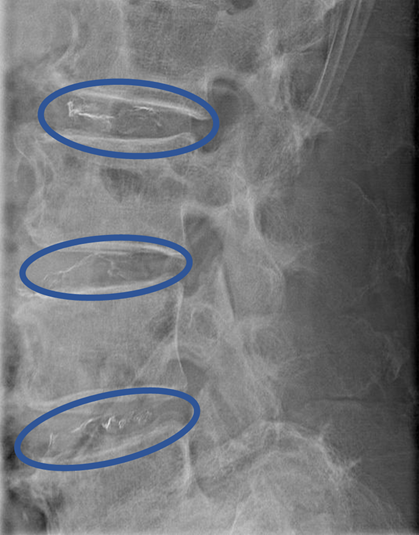

DiscoGelを入れた後の画像になります。

治療は30分程度で終了

回復室で休憩後、歩いて帰院されました。